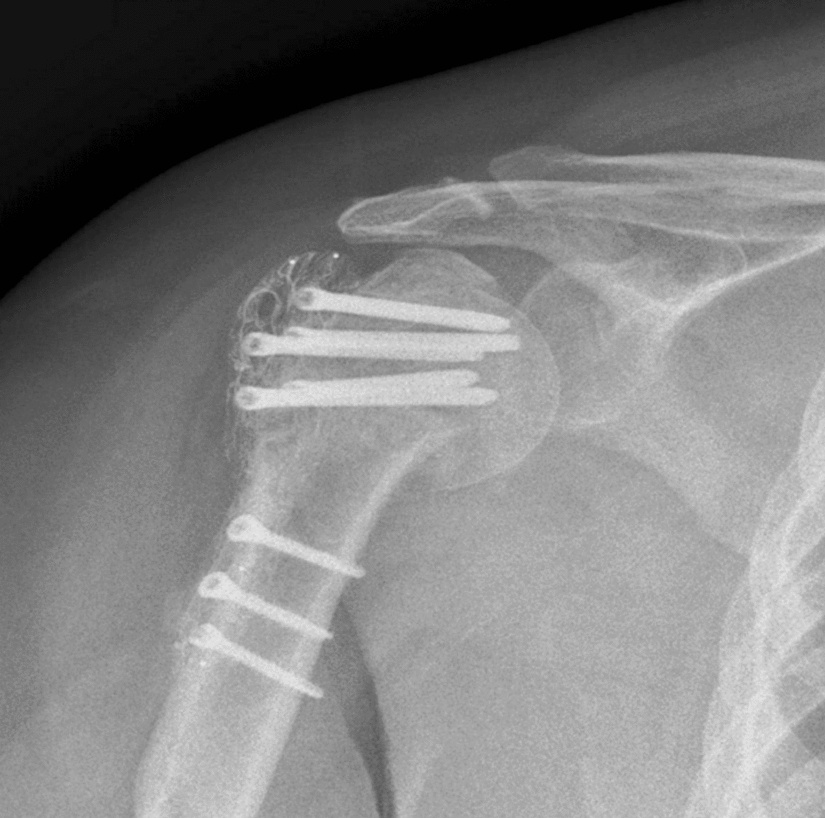

When we think about joint replacements or fracture fixation in orthopaedics, most people picture shiny metallic implants — often made of stainless steel, titanium alloys, or cobalt-chromium. These metals have been the gold standard for decades because they’re strong, durable, and well-tested. But metals also come with limitations: they’re much stiffer than bone, can cause imaging artefacts on X-rays and MRIs, and in rare cases, may trigger allergic reactions.

• Imaging challenges: Metallic implants show up brightly on X-rays and can create visual artefacts on CT and MRI scans, sometimes obscuring key details surgeons want to see post-operation.

• Radiolucency: Unlike metals, PEEK doesn’t block X-rays or create imaging artefacts. This allows for clearer visualization of the bone-implant interface, improving surgeons’ ability to assess healing and detect complications early.

• The radiolucency of PEEK offers a clear advantage for post-surgical imaging, enabling surgeons to monitor healing without the visual noise of metal artefacts.

Outside of joint replacements, PEEK plates are being explored for fracture fixation, where they may allow earlier weight bearing and faster rehabilitation with lower hardware removal rates. PEEK spacers and cages are also used in spine surgery with good early outcomes.